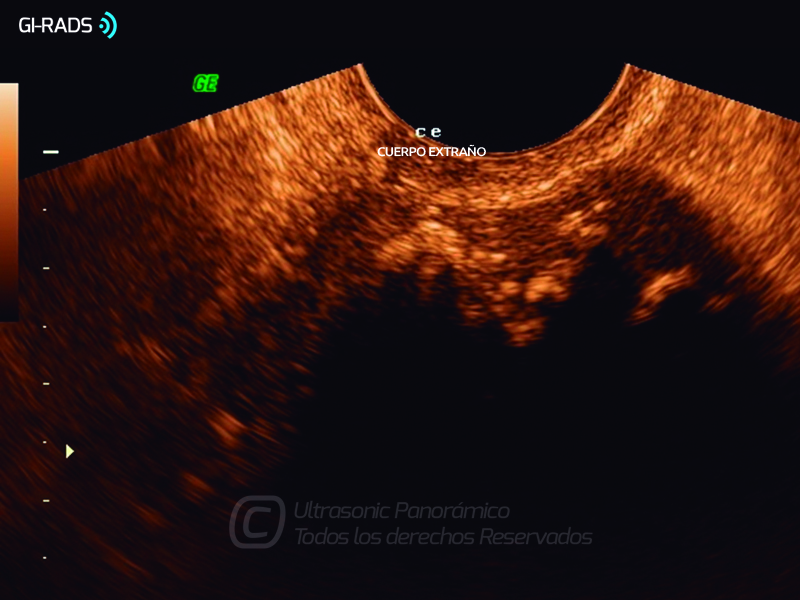

Patologías Benignas – Patología Extra-Ginecológica

• Patologías Benignas – Patología Extra-Ginecológica